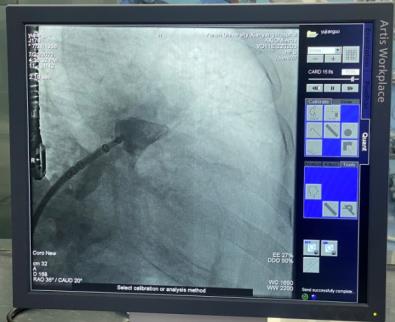

穿刺房間隔后置入6F豬尾導管,于CAU20°,RAO35°進行左心耳造影,可見左心耳為大角度反雞翅形,測量左心耳開口26mm,深度25mm。各位在線的專家有張玉順教授、宋治遠教授、胡浩教授等,進行了熱烈討論后,一致認為該例手術難度較大,封堵傘不易釋放。

經過仔細讀圖,發現左心耳下葉可作為封堵主軸向,該方向避免了大角度反折,但深度略淺,手術難度仍是不小。最終選取30mmWATCHMAN封堵器。